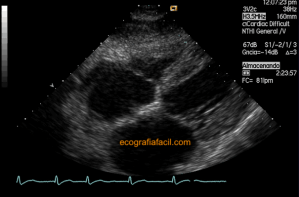

141. Mediciones de los planos paraesternales.